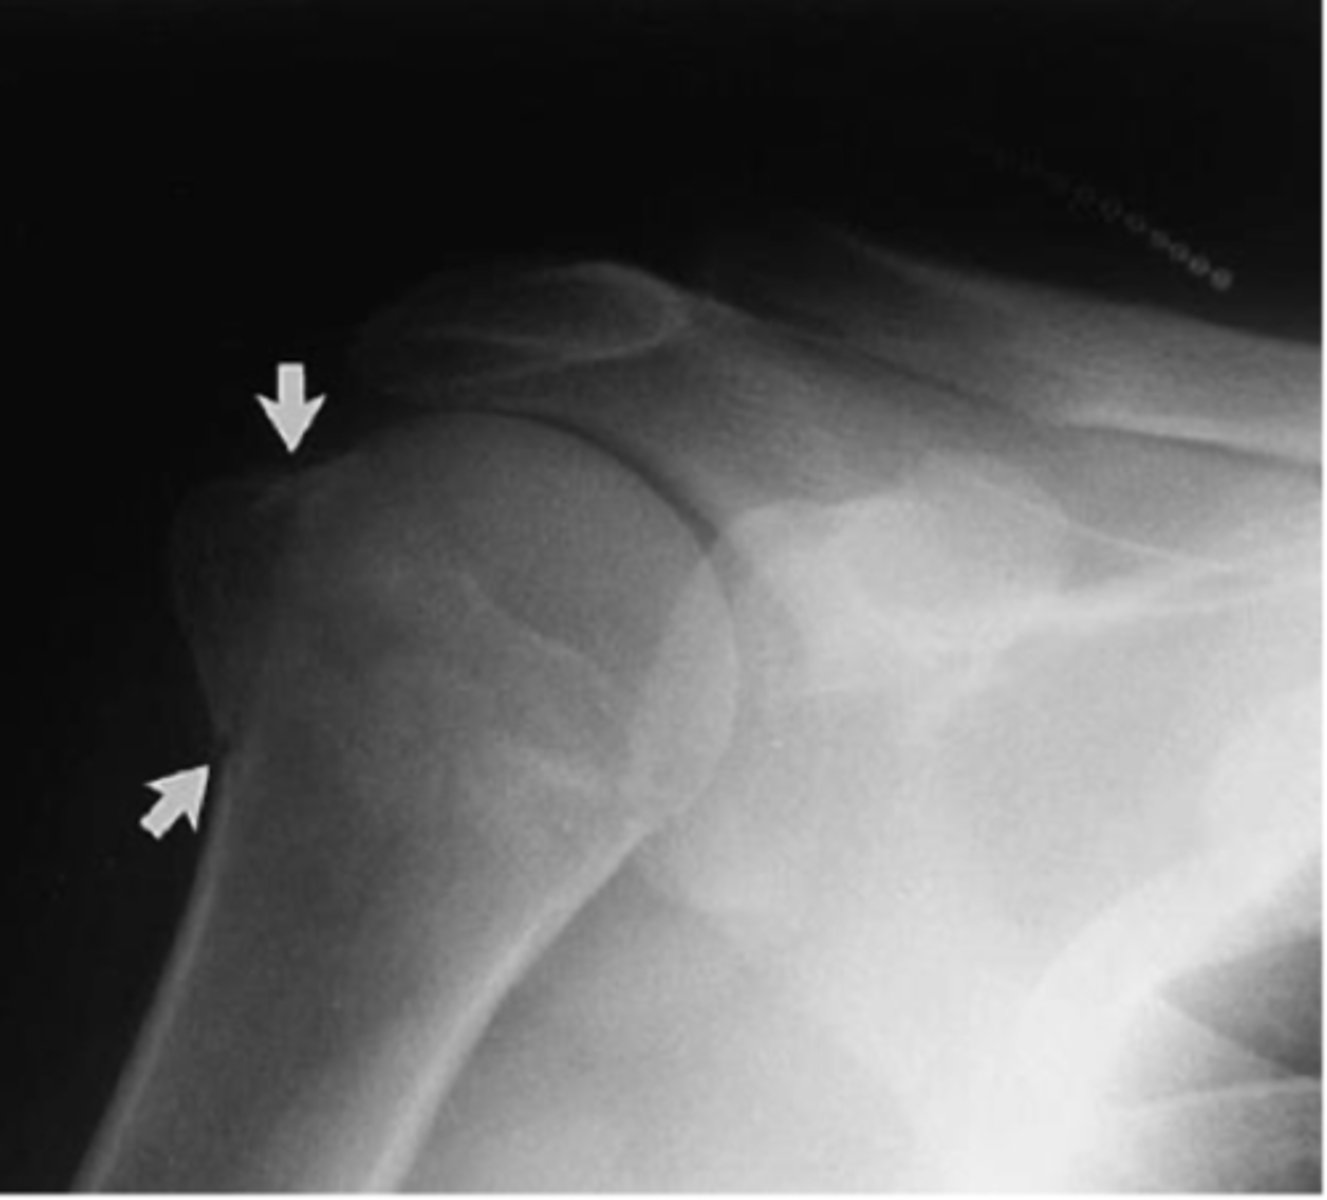

Undisplaced fracture of the greater tubercle

What is the issue?